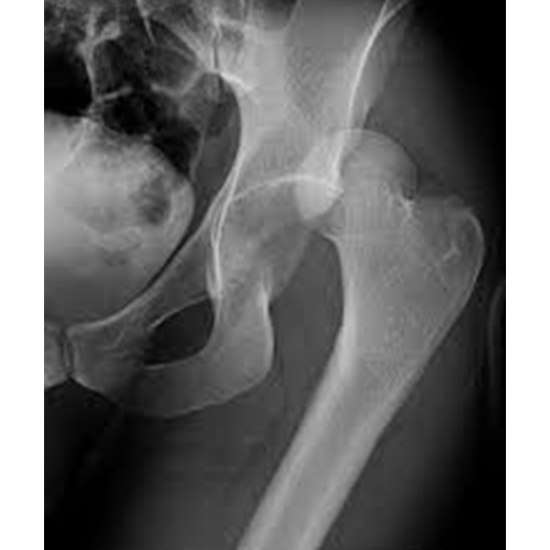

An X-ray of the hip is a way to see clearly how the femur bones fit together in the hip joint. From the side view of the hip, you can tell if there is a broken hip bone, a dislocation, a misalignment of the bones, or a degenerative condition of the hip joint.